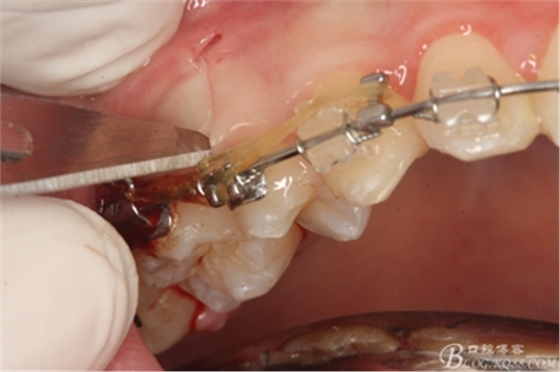

圖14.用小球鉆縱分15牙根

圖15 .微創(chuàng)挺把15牙根縱分成近遠(yuǎn)中兩塊

圖16.微創(chuàng)挺挺松近中根面部分,從16與14之間間隙出來

圖17.血管鉗取出近中部分15牙根